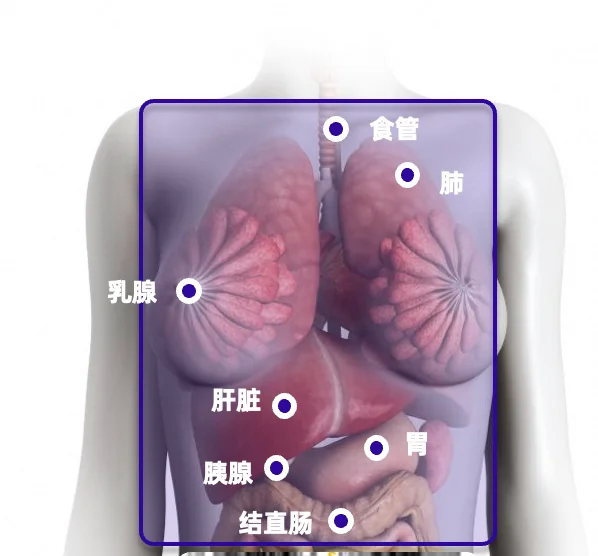

效率和价值的革新:阿里达摩院的“平扫CT+AI”技术,能在一次平扫CT中,快速识别胰腺癌、胃癌等多种癌症和急重症。